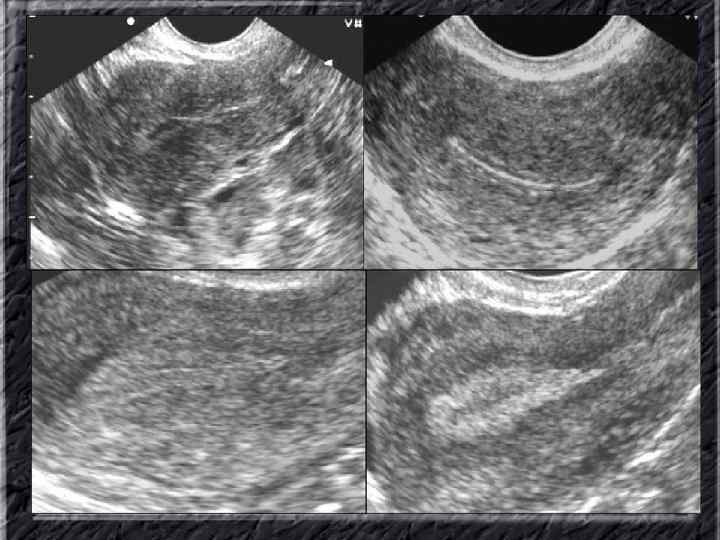

Названия слайдов: • • • Слайд 20. Ультрасонография: диффузная эхонеоднородность миометрия при внутреннем эндометриозе. Слайд 21. Эндометриоз матки: Пять маленьких очажков эндометриоза красно-коричневого цвета по задней поверхности матки; макропрепарат. Слайд 22. Множественная миома матки: видны субсерозные, субмукозные и интрамуральные узлы; макропрепарат. Слайд 23. Большая миома матки, подвергшаяся дегенеративным изменениям ( «красная дегенерация» ); макропрепарат. Слайд 24. Ультрасонография: интрамуральный узел фибромиомы, деформирующий контуры органа. Слайд 25. Ультрасонография: интрамуральный узел фибромиомы, деформирующий полость матки и смещающий эндометрий книзу. Слайд 26. Ультрасонография: субсерозный узел фибромиомы матки с эхопризнаками нарушения питания. Слайд 27. Лапароскопия: субсерозная фибромиома матки. Слайд 28. Лапароскопия: выраженный сосудистый рисунок на поверхности субсерозной фибромиомы матки. Слайд 29. Лапароскопия: выраженный сосудистый рисунок на поверхности субсерозной фибромиомы матки. Слайд 30. Большая цервикальная плоскоклеточная карцинома, которая простирается до влагалища; макропрепарат.

Названия слайдов: • • • Слайд 41. Лапароскопия: эндометриоидная киста яичника. Слайд 42. Лапароскопия: эндометриоидные гетеротопии на поверхности эндометриоидной кисты яичника. Слайд 43. Ультрасонография: поликистозное изменение яичника. Слайд 44. Серозная цистаденома яичника: внешний вид; макропрепарат. Слайд 45. Лапароскопия: цистаденома яичника. Слайд 46. Ультрасонография: папиллярная цистоаденома яичника, содержащая внутри папиллярные разрастания. Слайд 47. Ультраснография: многокамерная киста яичника (муцинозная цистаденома). Слайд 48. Лапароскопия: папиллярная цистаденома. Слайд 49. Ультрасонография: многокамерное жидкостное образование яичника, содержащее полиморфный солидный конгломерат — рак из муцинозной цистаденомы. Слайд 50. Рентгеноконтрастная сальпингография: нормальное наполнение и проходимость обеих маточных труб.

Названия слайдов: • • • Слайд 51. Ультрасонография: интерстициальный и истмический отделы маточной трубы. Слайд 52. Лапароскопия: неизмененная правая маточная труба. Слайд 53. Ультрасонография: многокамерная форма сальпингита. Слайд 54. Лапароскопия: относительно равномерное утолщение маточной трубы при гидросальпинксе. Слайд 55. Лапароскопия: вид маточной трубы при гидросальпинксе. Слайд 56. Гистеросальпингография: неравномерное расширение и деформация маточных труб. Слайд 57. Прервавшаяся трубная беременность: плод; макропрепарат. Слайд 58. Гематосальпингс, развившийся вследствие внутреннего разрыва плодо-вместилища при трубной беременности; макропрепарат. Слайд 59. Лапароскопия: значительное увеличение участка маточной трубы при трубной беременности. Слайд 60. Лапароскопия: скопление крови в полости малого таза в результате трубного аборта.

Названия слайдов: • • • • Слайд 61. Лапароскопия: множественные спайки в полости малого таза женщины. Слайд 62. Лапароскопия: признаки спаечной болезни в полости малого таза женщины. Слайд 63. Лапароскопия: деформация маточной трубы при спаечном процессе в полости малого таза. Слайд 64. Ультрасонография: спаечный процесс в малом тазу. Слайд 65. Ультрасонография: мультифолликулярные яичники. Слайд 66. Ультрасонография: кистома яичника. Слайд 67. Ультрасонография: патолоргия эндометрия. Слайд 68. Ультрасонография: внематочная беременность. Слайд 69. Ультрасонография: внематочная беременность. Слайд 70. Кольпоскопия: кандлилома – папиллома. Слайд 71. Кольпоскопия: кандлидозные бели. Слайд 72. Кольпоскопия: полип шейки матки. Слайд 73. Кольпоскопия: эрозия шейки матки. Слайд 74. Кольпоскопия: экспульсия ВМС.